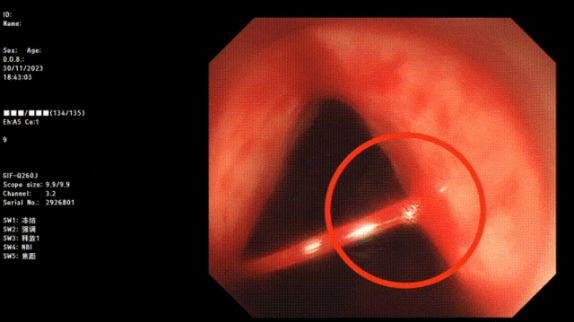

1. 内镜检查:包括胃镜、结肠镜等内镜检查技术,可以直接观察到消化道黏膜的情况,帮助医生确定出血的原因。

止血成功